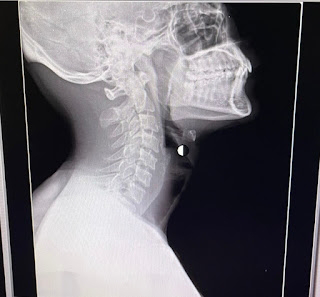

27 year old male with c/o headache

.A 27yrs old male came to casuality with c/o headache

and giddiness on and off since 3yrs

Patient was apparently asymptomatic 3yrs back then he sustained head injury RTA (bike vs bike). He was presented to hospital with swelling over left occipital region and seizure like activity there was loss of consciousness for 1hr not associated with ear or nose bleeding, vomiting .where they done

CT brain and was told to be normal.